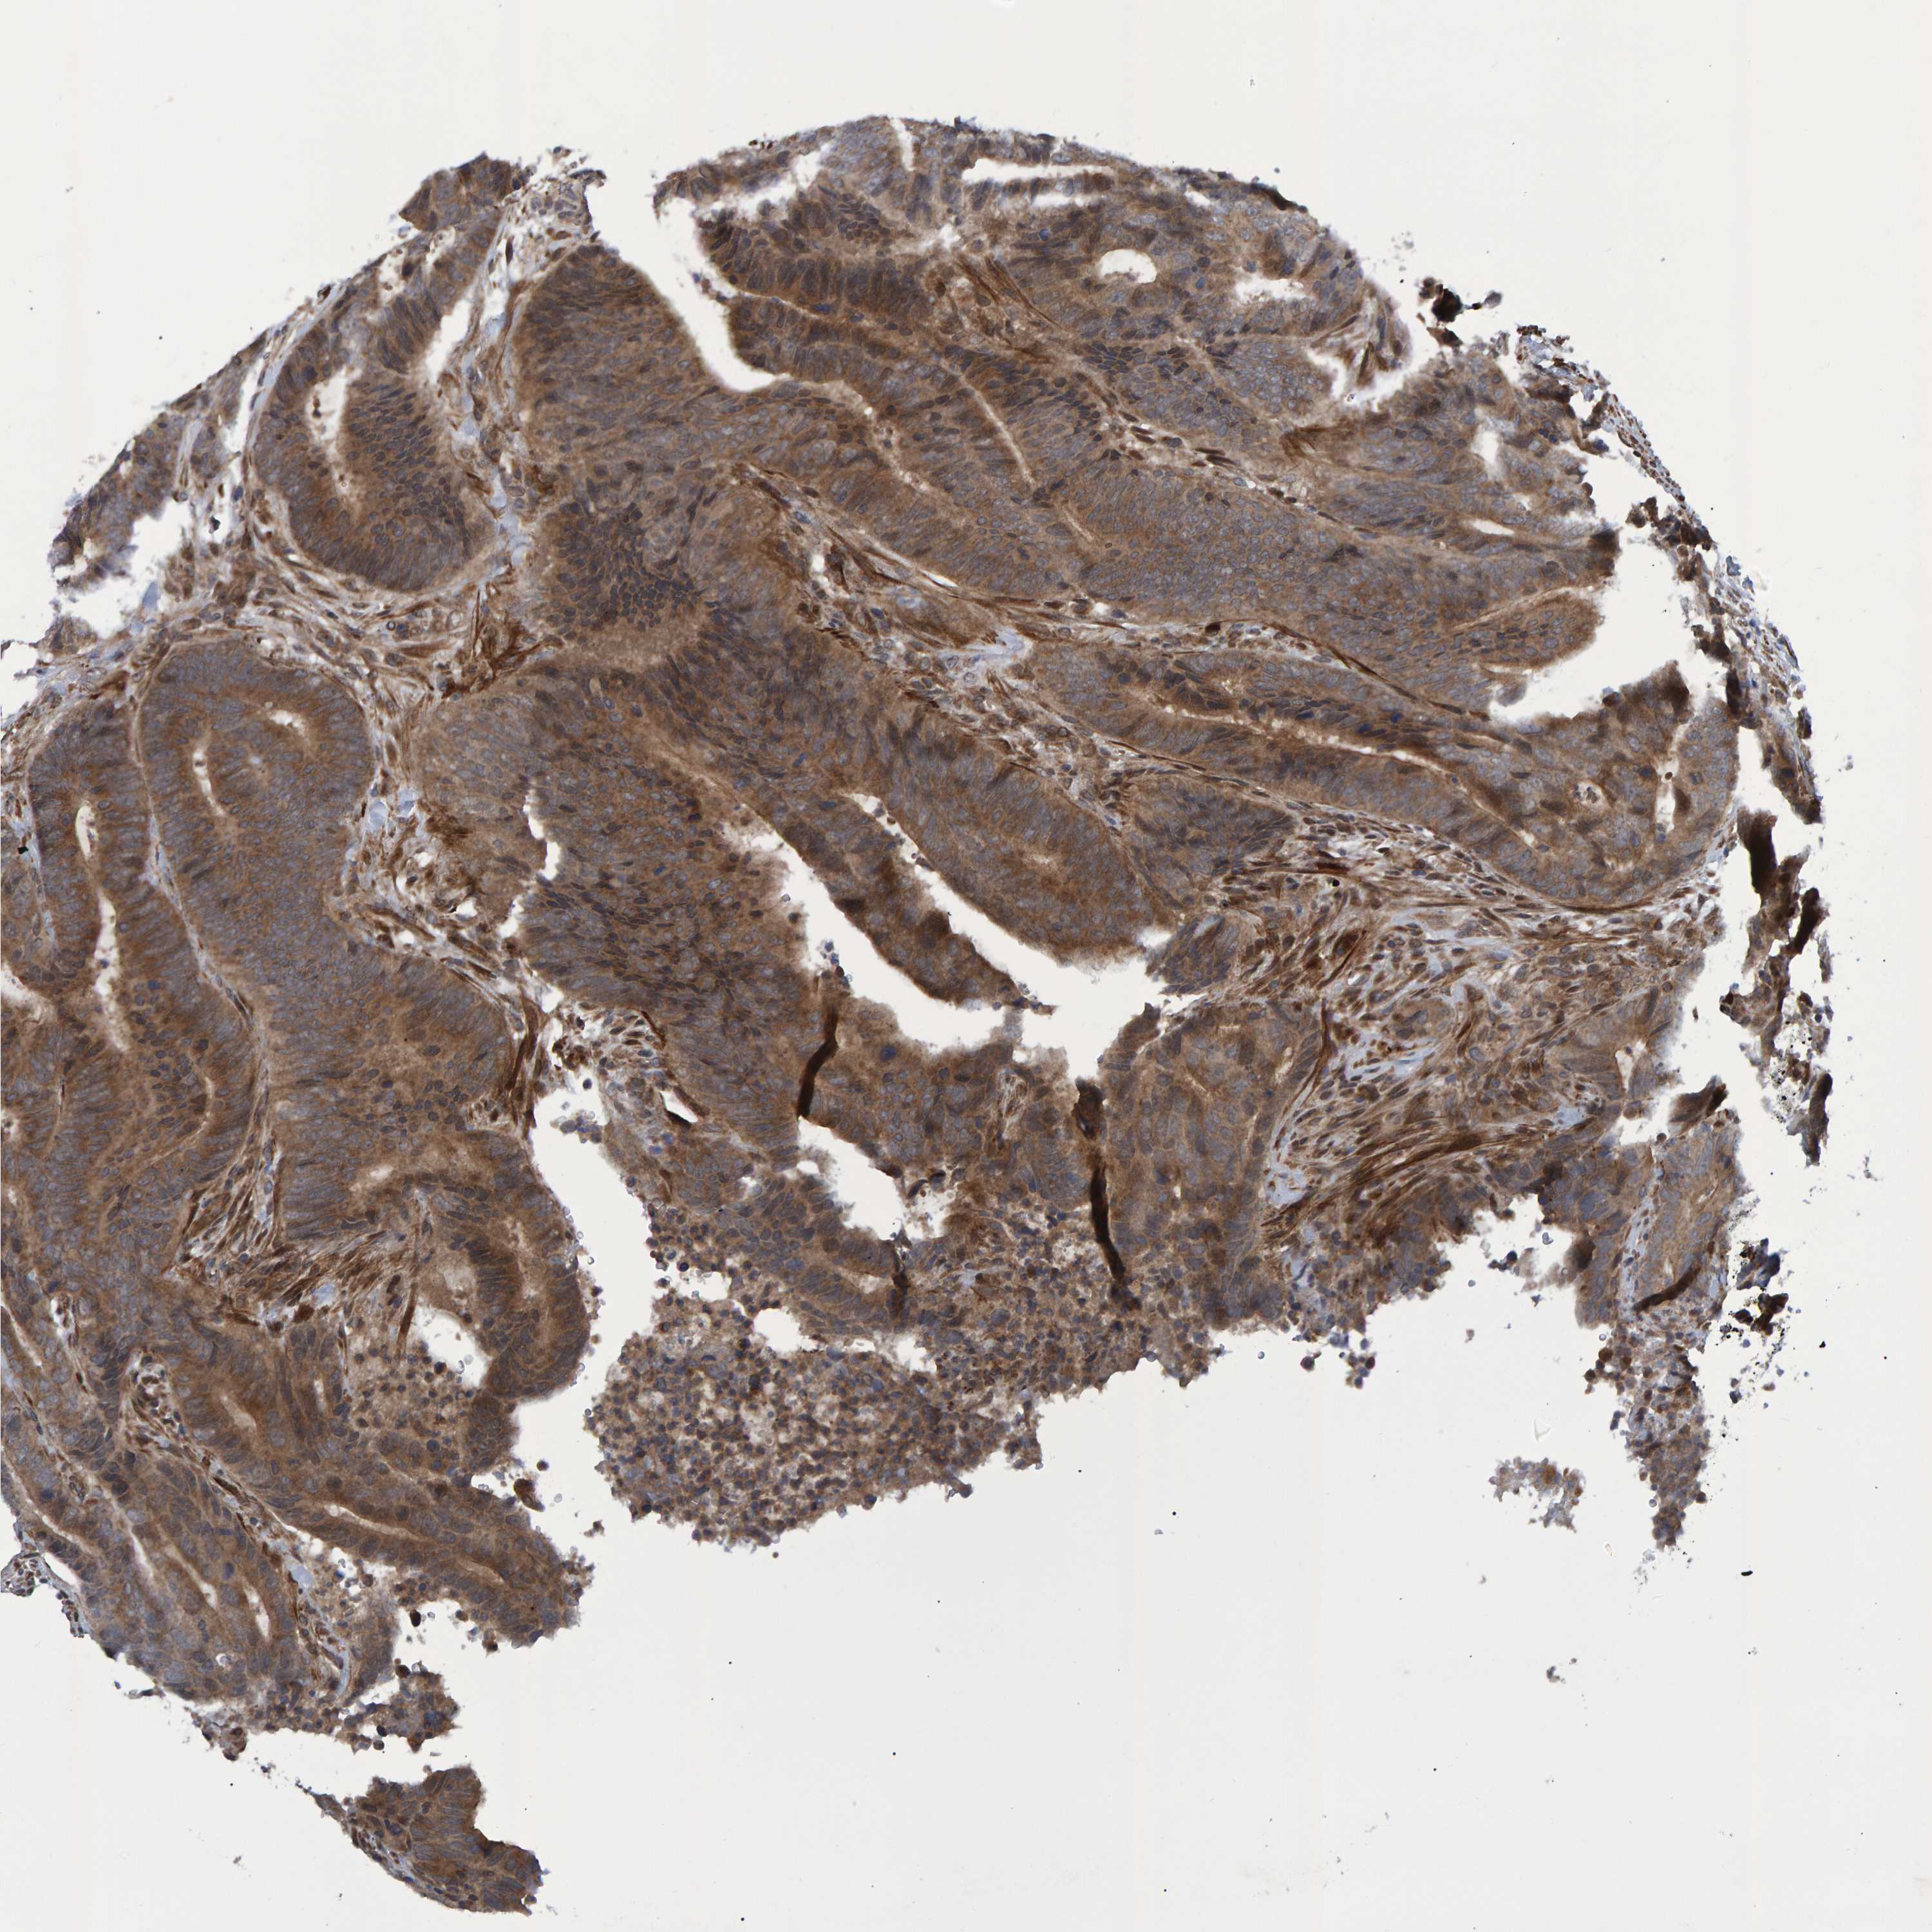

CANCER COLORECTAL CANCER Show tissue menu

Colorectal cancer

Human cancer

Colon adenocarcinoma